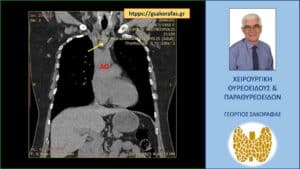

Όζος θυρεοειδούς πλήρως εξωφυτικός με βαθιά κατάδυση στο μεσοθωράκιο (κίτρινο βέλος). Εικόνα στην αξονική τομογραφία. Ο όζος φθάνει στις παρυφές του αορτικού τόξου (AO)

Αξονική τομογραφία

Στην αξονική τομογραφία που έγινε για την μέτρηση του βαθμού κατάδυσης, ο καταδυόμενος όζος απεικονίσθηκε οπισθοστερνικά στο ανώτερο πρόσθιο μεσοθωράκιο, αμέσως έμπροσθεν και άνωθεν της ανωνύμου αρτηρίας, στην έκφυσή της από το αορτικό τόξο, φθάνοντας στις παρυφές αυτού.